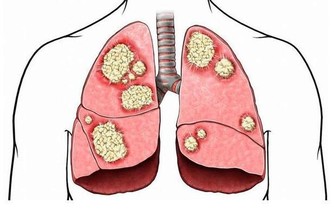

住在墨西哥聖盧卡斯岬的Mercedes Talamantes與她的巨型腫瘤一起生活了5年之久,

這位51歲的媽媽原本體重只有64公斤,但隨著腫瘤的成長,

Talamantes的身體就像是吹氣球般,體重來到了124公斤,

即便腫瘤都站了她的身體體重一半了,她仍然不願去看醫生。

直到在她其中一位女兒勸說下,才終於願意接受治療。

最後來到聖盧卡斯的IMSS醫院進行手術,經由醫療團隊的合力下才把這顆大腫瘤給取下。

Talamantes自己也承認過去2年來因為這顆巨大腫瘤逐漸增大,

使得她無法輕鬆走動,甚至無法順暢的呼吸,幸好現在把腫瘤移除掉,

Talamantes又能恢復原來正常的生活了。

由Gilberto Inzunza Salazar醫生所帶領的醫療團隊

一共耗費了4小時才終於取出這顆腫瘤,

他們發現這顆腫瘤是從其中一個卵巢開始成形,再慢慢移到她的腹腔。

而腫瘤一切除,Talamantes的體重也一下削減了一半。

現在醫生也終於能夠親眼目睹這顆重達132磅( 約60公斤 )的腫瘤,

幾乎是普通成年女性的體重,而且也只比Talamantes的體重輕4公斤而已!

她的醫療團隊認為這是有史以來最大的卵巢腫瘤,也是第一次看到這麼大的腫瘤。